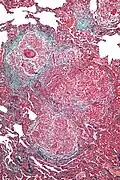

Additional images

High magnification micrograph of hypersensitivity pneumonitis showing granulomatous inflammation. Trichrome stain.

High magnification micrograph of hypersensitivity pneumonitis showing granulomatous inflammation. Trichrome stain.

Histopathology

The acute form can be characterized by poorly formed noncaseating interstitial granulomas and mononuclear cell infiltration in a peribronchial distribution with prominent giant cells.[1] The subacute, or intermittent, form produces more well-formed noncaseating granulomas, bronchiolitis with or without organizing pneumonia, and interstitial fibrosis.[1] Much like the pathogenesis of idiopathic pulmonary fibrosis (IPF), chronic HP is related to increased expression of Fas antigen and Fas ligand, leading to increased epithelial apoptosis activation in the alveoli.[21] Cholesterol clefts or asteroid bodies are present within or outside granulomas.[1]